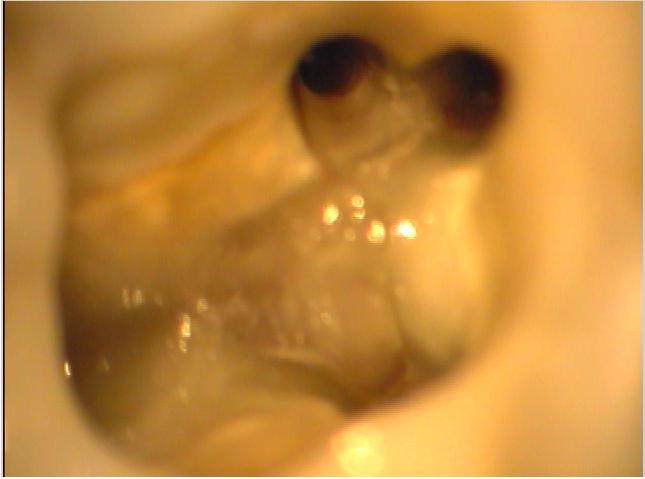

Klinische Situation nach abgeschlossener Aufbereitung

Vergrößerte Situation

Vergrößerte Situation; deutlich sind die 4 Kanaleingänge zu erkennen